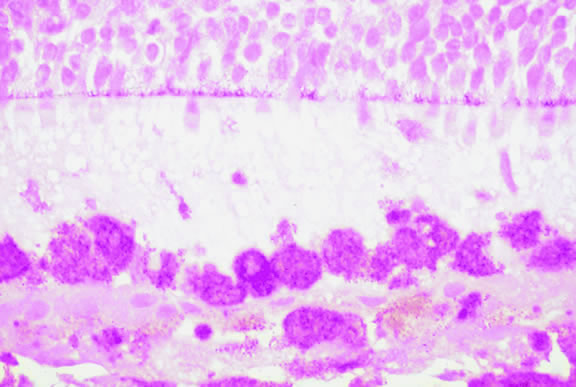

Choroidal melanomas produce abnormalities in the overlying retinal pigment epithelium including atrophy, hyperplasia, and the formation of drusen and drusenoid material.92 The overlying retina often shows photoreceptor loss and may develop cystoid edema. The latter tends to be more common in slower growing lesions, especially choroidal hemangiomas. After Bruch's membrane has ruptured, the vessels located in the mushrooming head of the tumor are often quite prominent, reflecting vascular stagnation caused by the compression at the waist of the tumor (see Fig. 22). Aggregates of macrophages that have ingested periodic acid-Schiff (PAS)-positive lipofuscin pigment and melanin from the damaged retinal pigment epithelium can be found in the subretinal fluid (Figs. 39 to 41). These are evident ophthalmoscopically as clumps of orange pigment that serve as a clinical marker for an actively growing neoplasm.80,81

Fig. 39. Juxtapapillary melanoma with orange pigment. Orange pigment is a clinical marker for an actively growing tumor.

Fig. 41. Orange pigment. Orange pigment is comprised of aggregates of macrophages that have phagocytized periodic acid-Schiff (PAS)-positive lipofuscin and melanin pigment released by retinal pigment epithelial cells that have been disrupted by the actively growing tumor. (Periodic acid-Schiff, × 100.)